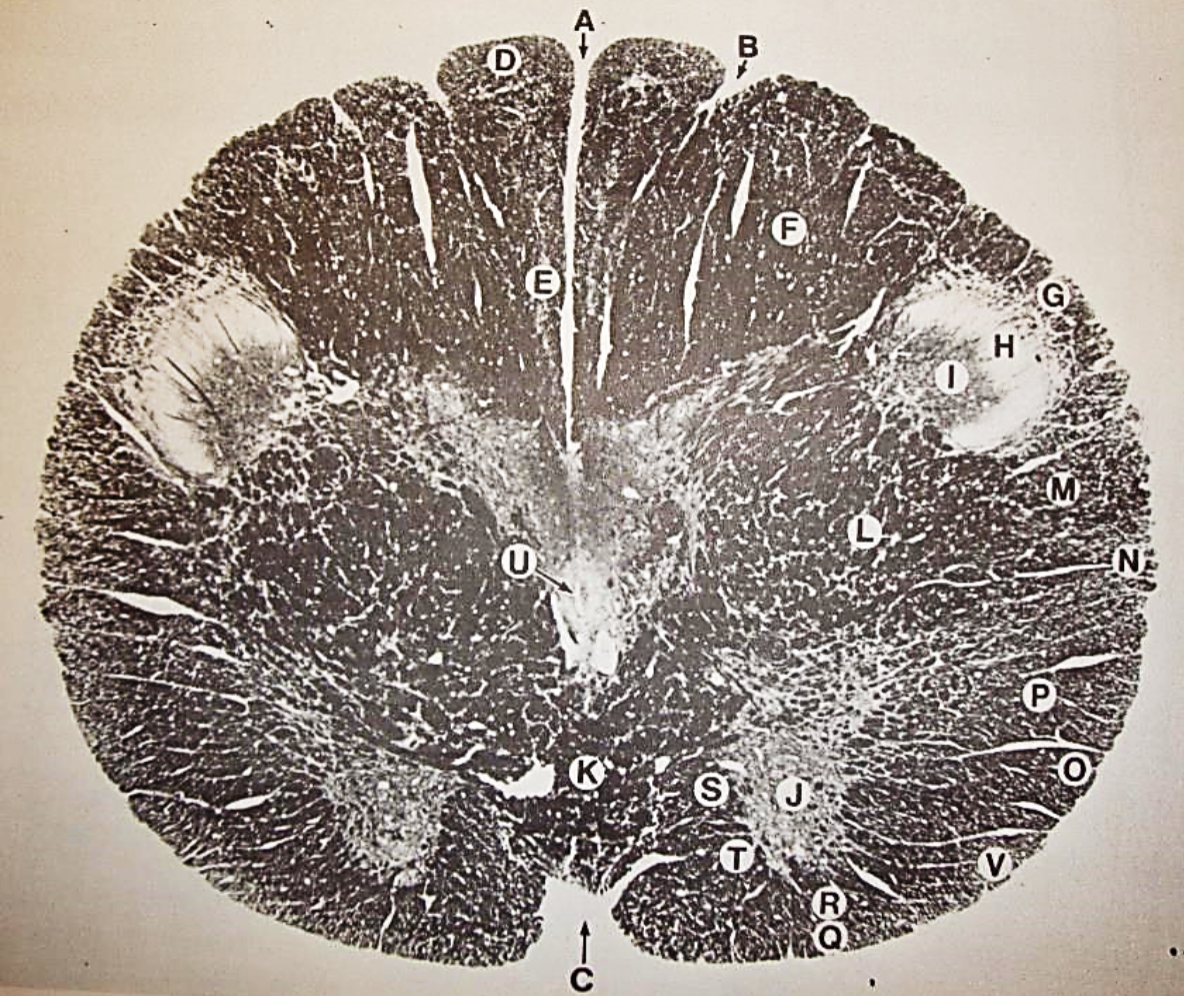

A

fasciculus gracilis

B

gracile nucleus

C

fasciculus cuneatus

D

cuneate nucleus

F

internal arcuate fibers

G

decussation of internal arcuate fibers

H

medial lemniscus

I

hypoglossal nucleus

J

dorsal motor nucleus vagus

K

solitary fasciculus

L

solitary nucleus

M

dorsal longitudinal fasciculus

N

spinal trigeminal tract

O

spinal trigeminal nucleus

P

posterior spinocerebellar tract

Q

anterior spinocerebellar tract

R

spinal lemniscus

S

lateral vestibulospinal tract

T

rubrospinal tract

U

lateral reticular nucleus

V

medial accessary olivary nucleus

W

pyramidal (corticospinal) tract

X

arcuate nucelus

Y

medial longitudinal fasciculus

Z

tectospinal tract

a

fascicles of hypoglossal nerve